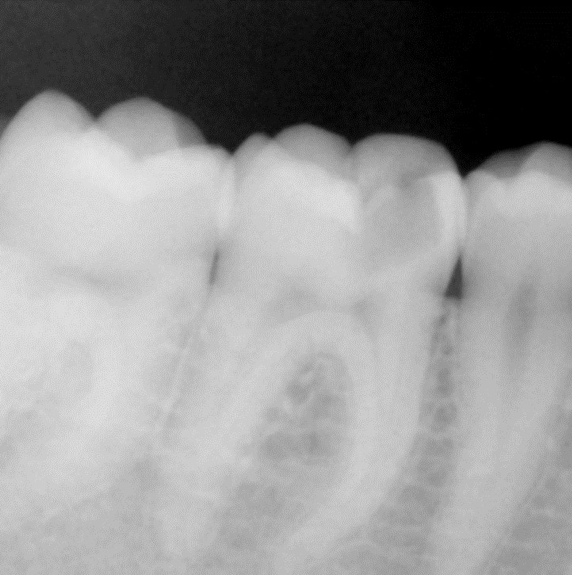

With a series of different finishing burs, the occlusal surface was finished and polished (Figure 10). The occlusion was verified. The occlusal surface was then smoothed with polishers and the restoration was polished with polishing paste. Post-operative radiograph revealed the extent of Predicta due to its excellent radiopacity (Figure 11).

Fig 11. Radiograph of the completed restoration